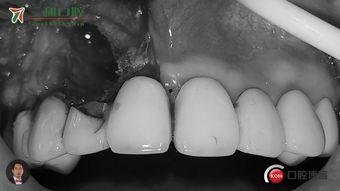

在视频里,我们可以看到医生在进行拔牙前,会仔细检查患者的口腔情况,确定埋伏牙的位置和大小。同时,医生还会向患者解释拔牙的过程和注意事项,确保患者充分了解并配合。

当一切准备就绪后,医生会使用专业的工具,小心翼翼地将埋伏牙从牙槽骨中取出。在这个过程中,我们可以看到医生的手法非常熟练,动作轻柔,尽量减少患者的痛苦。